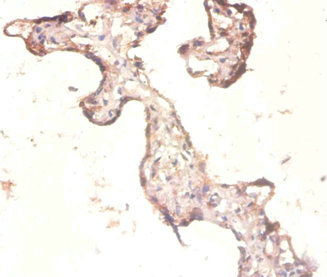

圖片:

應用范圍:ELISA, IHC

Application Recommended Dilution IHC 1:20-1:200 -